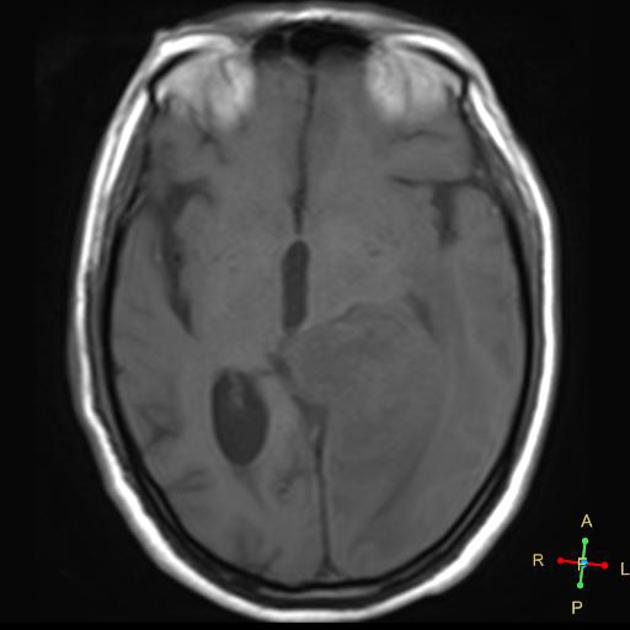

AA T1 without gadolinium

GBM T1 without gadolinium